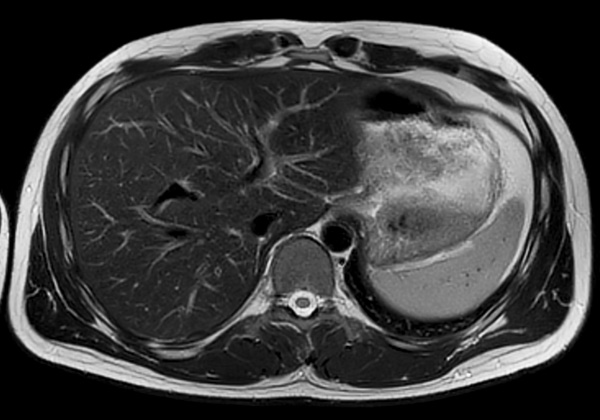

Axial T2w TSE